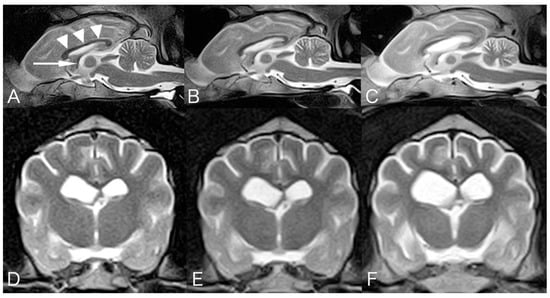

2. Case Presentation